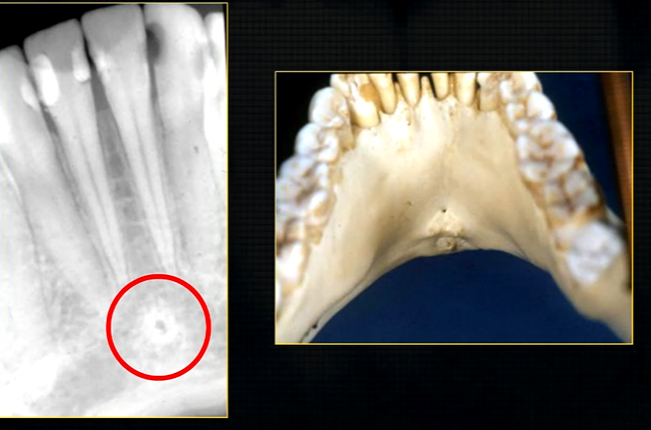

what does this anterior periapical graph show?

oval radiolucent area between the central incisors - is it Infront of the teeth (buccally?) or is it behind them? - you can’t tell radiographically

but its shape and position is compatible with the palatally positioned with the nasopalatine formaina

more posteriorly - radiopacities indicate the nasal septum and floor of the nose

dense, thin , white line in the middle of the image is the nasal septum

less dense opacity is caused by the

inferior nasal concha

radiolucency - nasal septum

lateral wall of the nose

maxillary air sinus

mid-palatal suture

this increased radiopacity is caused by the soft tissues at the tip of the nose - shadow - dense tissue